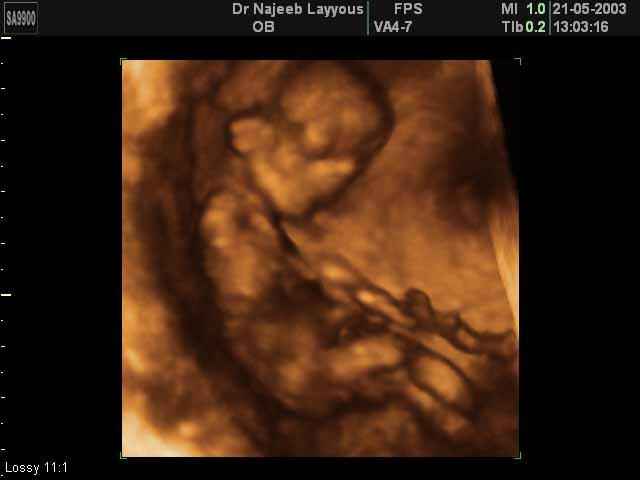

- Fetal Behavior Ultrasound Photos

Ultrasound Photos in 3D showing Fetal Behavior Inside the uterus | Dr N Layyous